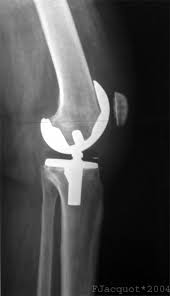

The company ORTHOPEDIC NIKIFOROV was founded in 1998 by the candidate of medical sciences. doctor of orthopedic-traumatologist of the highest category Nikiforov IA Owing to high professionalism and results of work, ORTONIC has gained well-deserved reputation and reputation among colleagues and population of Dnepropetrovsk region and CIS countries (Russia, Moldova, Armenia, etc.). The principle of the enterprise is NO IMPOSSIBLE, it is based on knowledge, experience and active implementation of modern technologies in orthopedics and traumatology. Conservative methods of treatment include individual selection of medicines, therapeutic blockades, manual therapy, massage, physiotherapy (vibration table, magnetotherapy, bioptron, electromyostimulation, etc.), rehabilitation with the suggestion of the necessary concomitant devices and means for the fastest recovery (corsets, bandages, various joint fixators, crutches, walking sticks, etc.). Various minor invasive interventions (chymonucleolysis, vertebroplasty, kyphoplasty, percutaneous nucleoplasty using cold plasma) that are performed on an outpatient basis are successfully used to treat problems associated with spine pathology. The latest modern treatment methods introduced in our company are endoscopic operations using the TYSSES technique of Joimax (Germany) with intervertebral hernias, stenosis and other pathologies of the spine, which allow to avoid complications occurring during open operations and the accompanying general anesthesia. We have many years of successful experience in traditional and modern minimally invasive endoprosthetics of large and small joints, which remains the main direction of our activity. Our company is the exclusive representative of the German company IO International Orthopaedics Holding GmbH, which based on the already known prostheses, its ideas and technological capabilities, has developed and implemented a new concept in hip replacement - an artificial joint prosthesis (ICON). We assist interested colleagues in training the operative technique for installing an artificial joint prosthesis - ICON, both in the workplace and in Germany. For 20 years we have been successfully cooperating with Sanitatshaus Gerd Klinz ortho team, an enterprise that for 20 years has been one of the leading places in Germany for the production of functional prostheses of the upper and lower limbs, as well as cosmetic prostheses of limbs and other body parts (nose, ears, eyeballs, fingers). We have an atmosphere of friendliness and human participation. Politeness, benevolence, the desire to understand and help is the basis of our attitude towards patients. We are always glad to see you and will do our best to make you feel great! We are waiting for you at: Ukraine, Dnepr, Gagarin Ave., 13 (under reconstruction) on all questions to address: tel .: +38 (050) 488-88-92 E-mail: orthonik.ukr@gmail.com Germany, Spine Nano Klinik, Zeppelinstr. 21, Potsdam Tel. +4901801121919 E-mail: kmw.nikiforov@hotmail.de